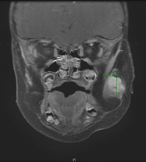

Metastatic melanoma vs lymphoma. Using a sentinel lymph node biopsy a diagnostic tool

Anjana Kaur and others

Journal of Surgical Case Reports, Volume 2019, Issue 4, April 2019, rjz117, https://doi.org/10.1093/jscr/rjz117